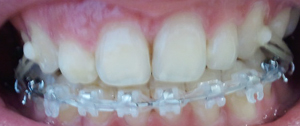

이번 월치료에는 하악 철사를 바꾸고^^~ 상악은 잇몸때문에 못부쳤던 교정기를 부치고 철사를 다시 끼웠어요^^

그리고 보시다 시피 저도 이제 고무줄을 밥먹을 때 빼고 걸고있어요ㅠㅠ